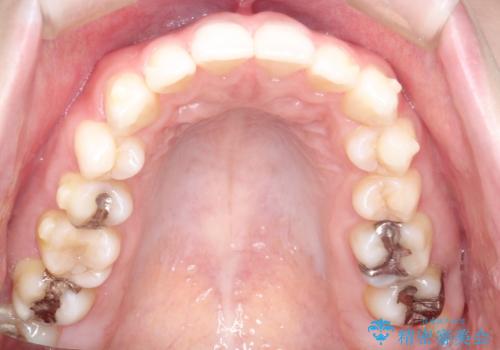

使用時間を守っていただけたので、スムーズに治療を終わることができました。

1周目が終わり、かなり綺麗になりましたがもう少し納得出来るまで続けたいという要望に答えてくださり、今2周目を終え本当に満足いく結果になりました。ありがとうございます。矯正を通して歯は意外と簡単に動くのだなと身をもって感じたのでこれからもリテーナーを怠らずつけ続けたいと思います。